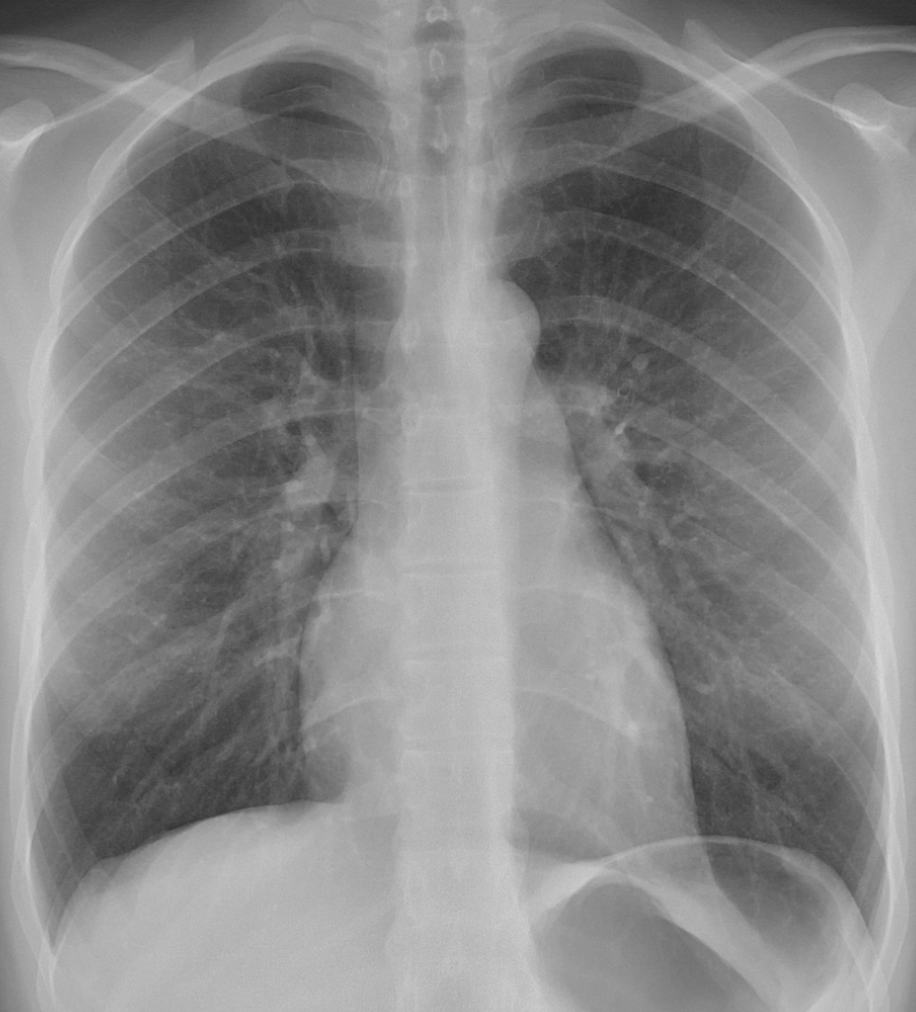

X-Rays: These tests can be used for a variety of different purposes however when being used to diagnose Lupus, doctors look at tissues and organs that may be damaged due to Lupus. For example, fluid or swelling in the lungs may be a sign of Lupus.